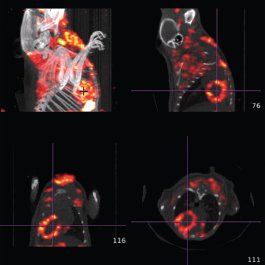

Das voll integrierte CT bietet niedrige Dosis mit Scanfunktionen (80 um und 160μm Pixelgröße) und Zykluszeiten von ~ 40-60 Sek. für eine Maus und 1-2 min. für eine Ratte. Das CT wird für die 3D-SPECT-oder PET-Field of View-Auswahl über eine patentierte einfache grafische Schnittstelle verwendet. Automatische, markierungsfreie Fusion von 3D SPECT- oder 3D-PET-Bilder mit 3D-Röntgen-CT-Bildern ist ein Standard-Feature bei U-SPECT-II / CT und Vektor / CT.